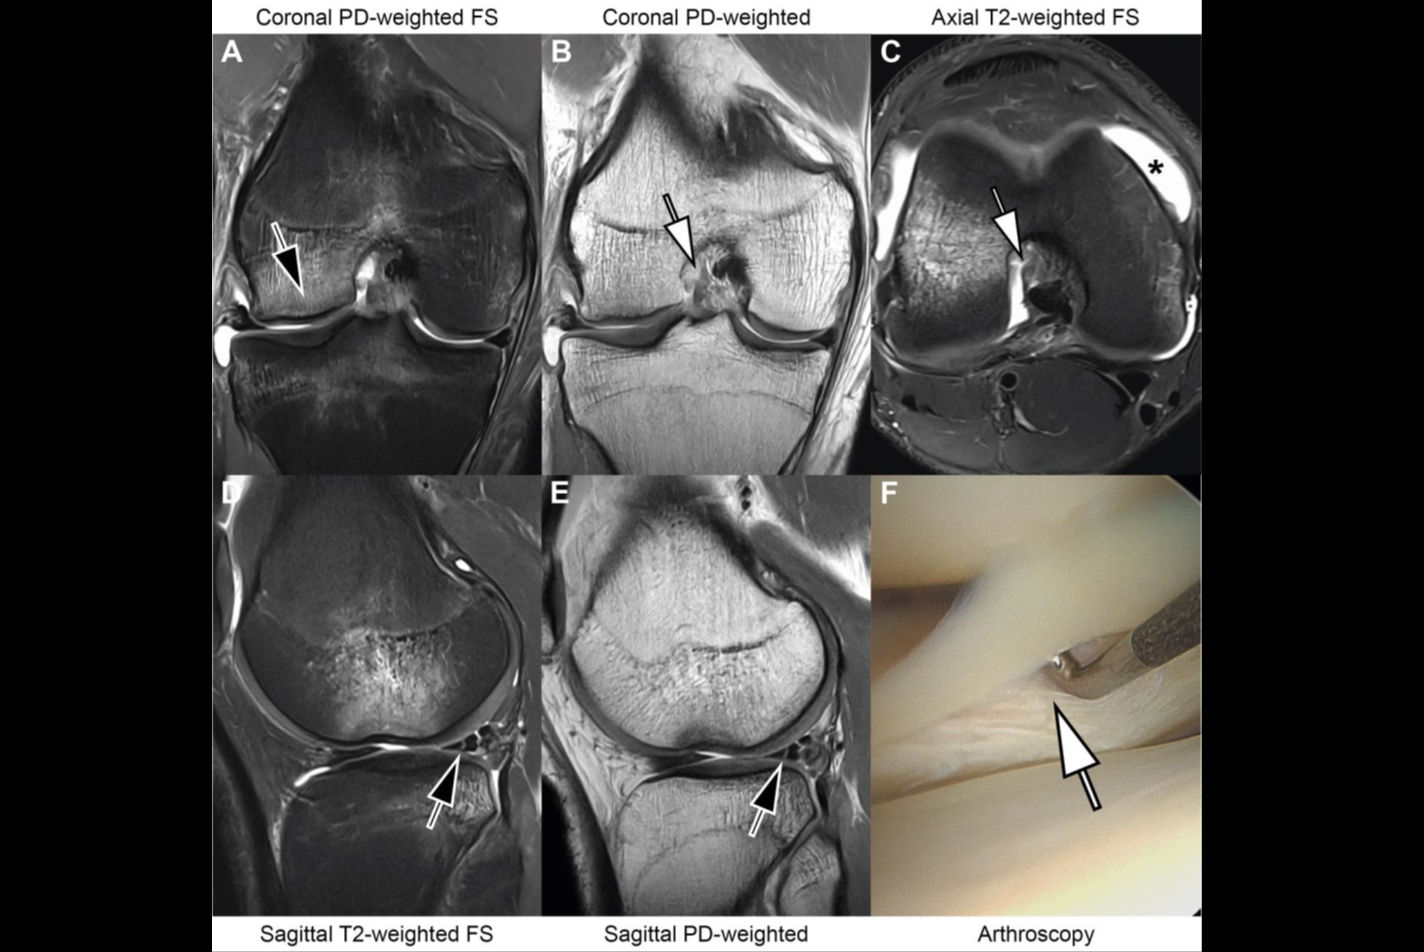

When it comes to the noninvasive diagnosis of acute and chronic knee abnormalities, MRI is the gold standard. There’s a strong push right now toward shorter examination times, and deep learning can help in this regard, according to research published on 23 April.